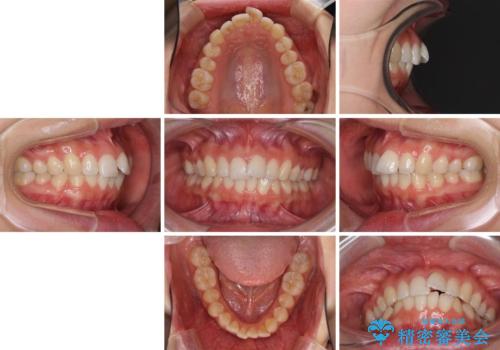

口が閉じにくい 1本飛び出した前歯の矯正治療

- 1本飛び出した前歯を治したいとのことで来院された患者様です。

歯列全体の拡大とIPR(歯と歯の間を削る)によってデコボコが解消するようにし、さらにゴムかけを活用して右側の咬み合わせ位置を変えるように設計し、インビザラインにより治療を行うこととしました。

結婚式までに前歯を整えたいとのことでしたが、インビザラインでは先に奥歯を移動させてから前歯を動かすため、間に合わない可能性がありました。しかし、結婚式までに期間があったことと、マウスピースをしっかりと装着してくださったことで、十分な歯列に整えることができました。

楽しく通院していただき、辛いと思っていた治療もあっという間であったそうで、患者様には大変満足していただきました。